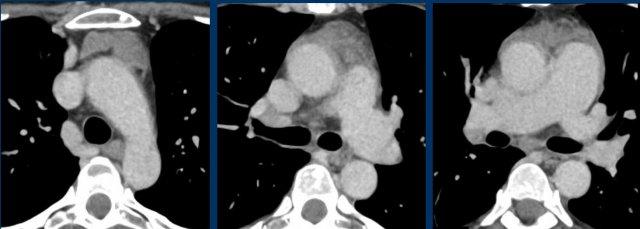

Các hình ảnh này của một phụ nữ 65 tuổi có tiền sử mắc bệnh Graves, một rối loạn tự miễn liên quan đến tình trạng cường chức năng tuyến giáp.

CT được thực hiện vì lý do ho ra máu.

Có một tuyến ức to lớn, cồng kềnh chứa mô mỡ đại thể.

Đây là hình ảnh điển hình của tăng sản tuyến ức.

Tăng sản tuyến ức trong bệnh Graves có liên quan đến tình trạng dư thừa hormone tuyến giáp và kháng thể kháng thụ thể thyrotropin.

Tình trạng này thường cải thiện sau khi điều trị thành công bệnh Graves.

Mặc dù không thực sự cần thiết, MRI vẫn được thực hiện.

Hình ảnh chuỗi xung gradient-echo nhanh pha đối (out-of-phase) cho thấy sự mất tín hiệu như dự kiến.

CT cho thấy tuyến ức trở về bình thường sau khi điều trị bệnh Graves.